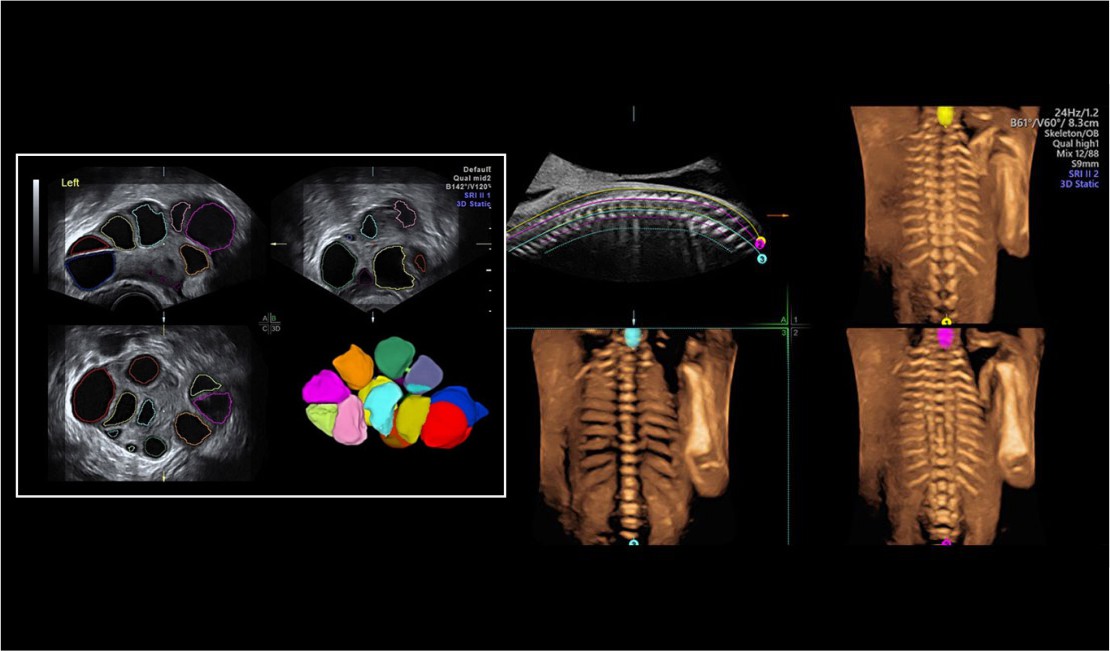

Unlike a traditional 2-D ultrasound, a 3-D ultrasound allows your doctor to see the width, height, and depth of the fetus and your organs. This ultrasound can be especially helpful in diagnosing any suspected problems during your pregnancy.

A 3-D ultrasound follows the same procedure as a standard ultrasound, but it uses a special probe and software to create the 3-D image. It also requires special training for the technician, so it may not be as widely available.